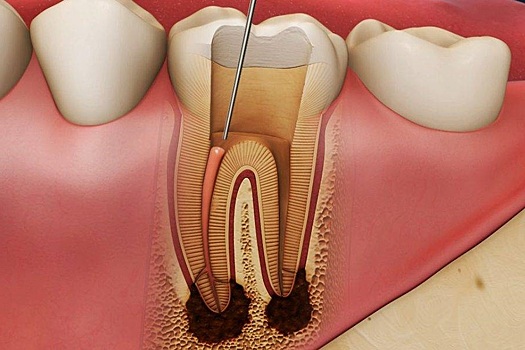

Нерв, также известный как сосудисто-нервный пучок, находится в зубе не случайно. Он формируется вместе с развитием зубов и одна из его функций заключается в контроле этого процесса и стимулировании роста зуба.

Вторая важная функция нерва в зубе – питательная или трофическая. За счет кровотока в зуб поступают необходимые микроэлементы, необходимые для поддержания жизнеспособности зуба.

Нерв также выполняет сенсорную функцию. Благодаря этой функции зуб реагирует на различные раздражители, такие как холод или горячее питание, а также механическое воздействие. Если возникают неприятные ощущения, человек обращается к стоматологу для своевременного лечения.

Кроме того, нерв имеет иммунную функцию. Если бактерии из кариозной полости проникают к нерву зуба, иммунные клетки из кровеносного русла направляются на их уничтожение. Это предотвращает развитие воспаления, защищая нерв и предотвращая появление пульпита.